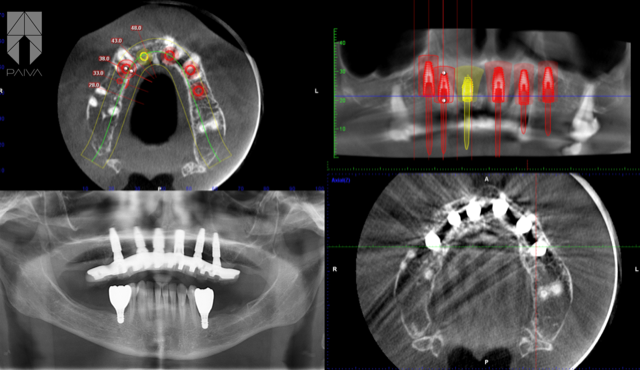

Une planification et une exécution soignées de chaque étape du diagnostic et du traitement sont des conditions qui garantissent le succès des grandes réhabilitations. Dans ce cas, il était nécessaire d’extraire les dents présentes, qui malheureusement n’était pas réparables.

Face à ce plan de traitement, nous avons décidé de procéder à l’implantation de 6 implants concomitante aux extractions dentaires, suivi de la pose immédiate d’une prothèse fixe sur les implants.

Une période de cicatrisation tissulaire et osseuse de 4 à 6 mois est nécessaire avant de réaliser la nouvelle prothèse définitive.

Les implants nécessitent d’un entretien régulier par le dentiste et un soin quotidien de la part du patient. Les études scientifiques montrent des taux de succès supérieures à 96% pour ces techniques implantaires. La longévité est liée à divers facteurs comme l’hygiène buccale et les conditions systémiques préexistantes.